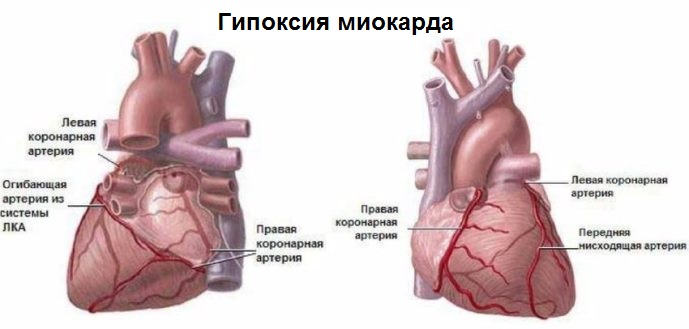

Особенности и диагностика левостороннего кровотока